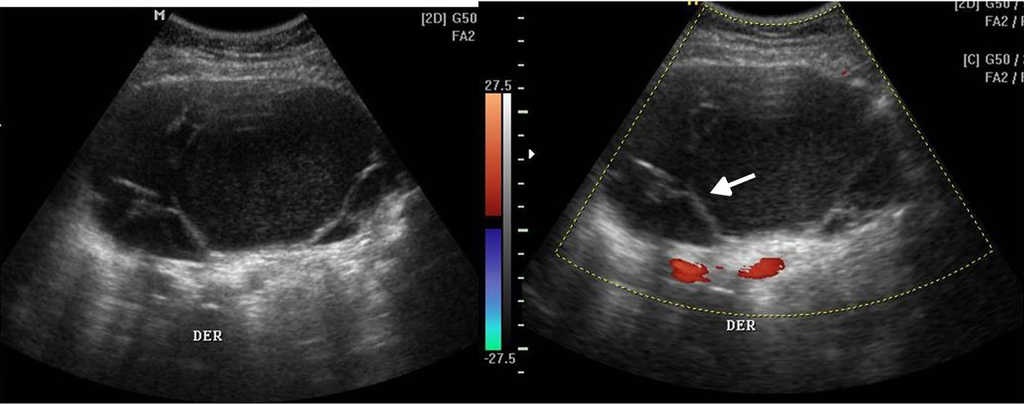

La ecograf??a determina la naturaleza s??lida o qu??stica de las masas anexiales, la presencia de septos o elementos s??lidos, y su vascularizaci??n con la exploraci??n Doppler (fig. 4). Estos hallazgos ayudan a determinar la benignidad o malignidad de la masa5,10.